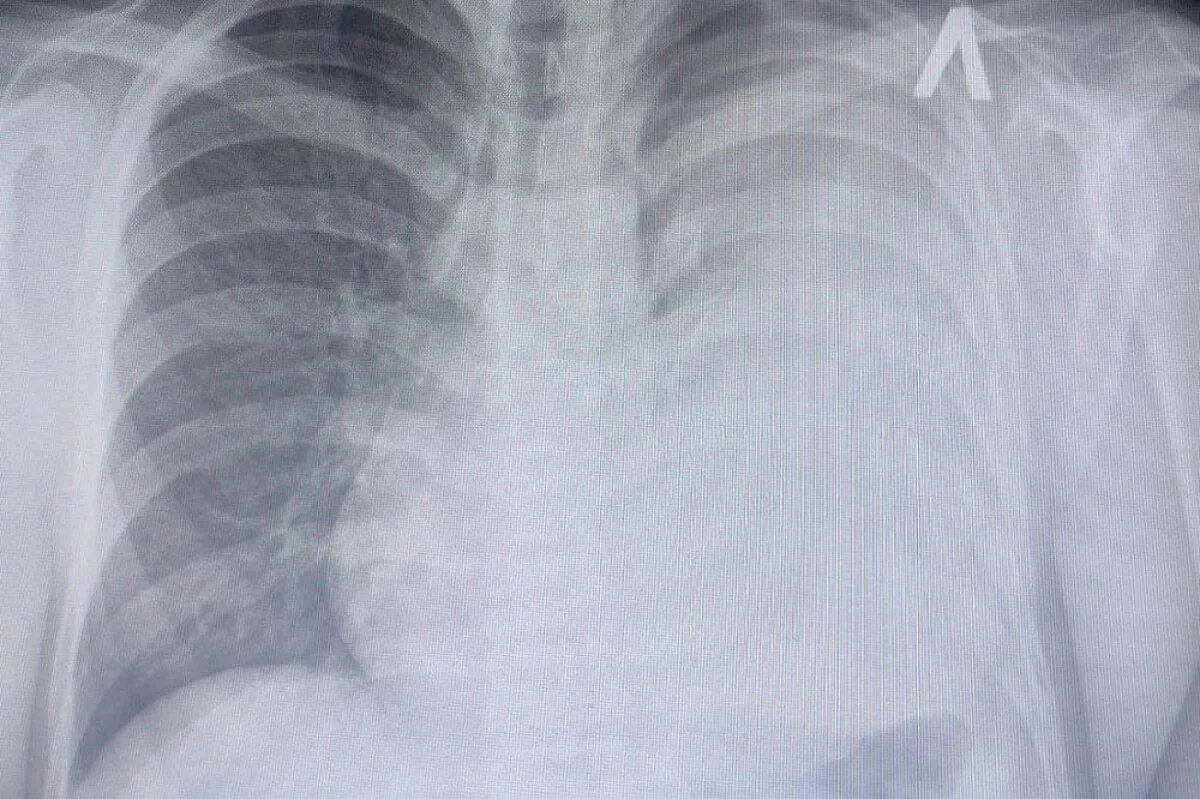

Врачи Ставрополя нашли литр жидкости в лёгких 18-летнего парня

При обследовании у ставропольца в левом лёгком нашли литр жидкости. Его отправили в пульмонологическое отделение. Высока вероятность того, что у пациента онкология.